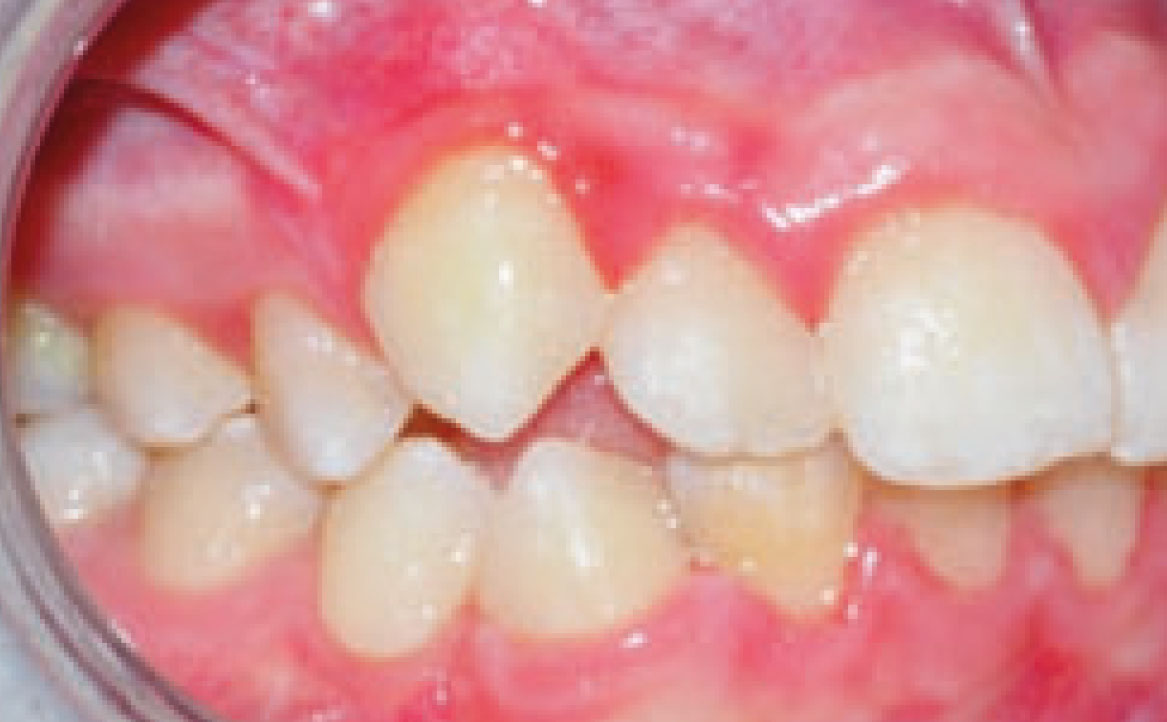

Inoltre, dall’analisi del volto si evidenziava la presenza di una mandibola leggermente retrusa. Ciò è stato confermato dalla teleradiografia latero-laterale, attraverso la quale è stata osservata una condizione di normo-divergenza con una tendenza all’iper-divergenza, con una condizione di seconda classe scheletrica, valutando gli angoli SNB ed ANB, le cui misure risultano essere rispettivamente di 75,5° e 4,5° (fig. 2).

La teleradiografia latero-laterale confermava il sospetto di una seconda classe scheletrica, con angoli SNB e ANB rispettivamente di 77° e 5°, con un aumento della pro-inclinazione degli incisivi superiore e un aumento dell’overjet, corrispondente a circa 6 mm (fig. 6).

Il confronto con le teleradiografie precedenti ha dimostrato che, tramite il trattamento con Invisalign®, è stata ottenuta una risoluzione della classe scheletrica ed un’armonizzazione dei tessuti, con riduzione dei valori di Overjet, Overbite e ANB.